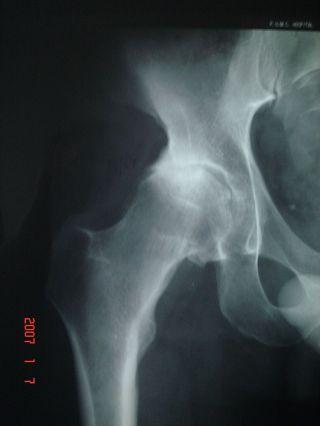

The detail would be "femoral-acetabular impingement of the cam variety", according to Dr. Brockwell. Looking back, I can see symptoms starting over 10 years ago. I would notice myself limping slightly after frisbee practice or training runs, despite not having any pain. Walking up stairs I noticed I was naturally taking steps 2 at a time with my left leg but only one at a time with the right. I had what felt like a minor muscle pull in the lower back on the right side that never got better with rest or worse with use. And the right shoe was getting harder and harder to reach to tie.

In early spring of '03 I was at the doctor for some other minor thing, and as I was set to go mentioned I had been growing increasingly stiff. The doctor asked to check, and was shocked at what he found - I was unable to cross my legs, there was almost zero abduction (leg moving out). They took x-rays, and I overheard one doctor exclaim to another he had not seen a joint like that on anyone less than 80 years old.

Though the x-rays looked bad and I was unable to continue participation in sports, things could have been worse. My only symptom was stiffness and an accompanying limp, right to the end there was never any pain. The week of the operation I was still able to go for long (2-hour) walks, day hikes, and bicycling (though getting on and off the bike was not easy).